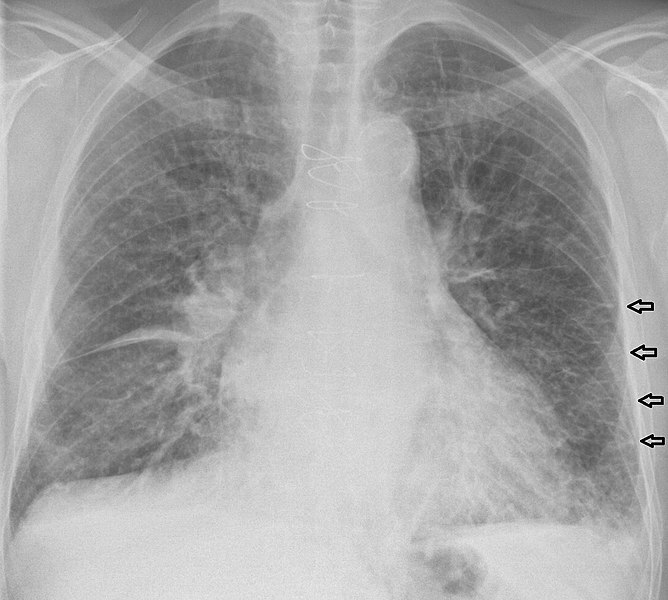

Q

what does this CXR show?

A

tension pneumothorax

- mediastinal shift to right

- absent lung markings